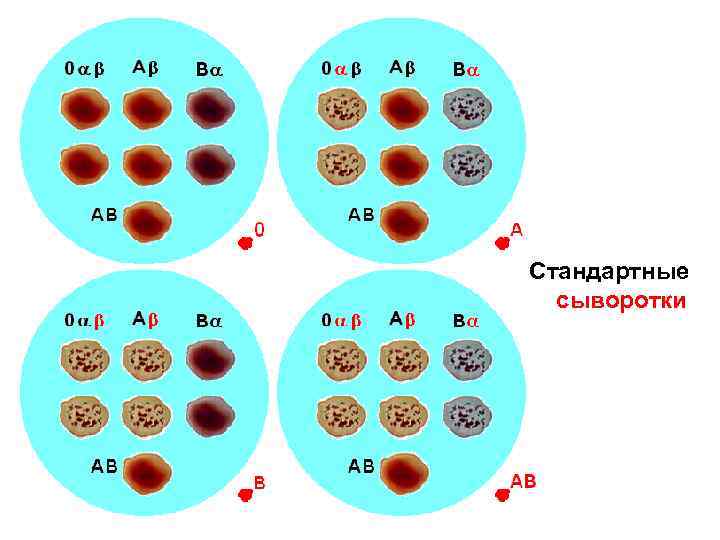

Вопрос 10 Система AB 0

Вопрос 10 Система AB 0

Стандартные сыворотки

Стандартные сыворотки

Отмытые стандартные эритроциты

Отмытые стандартные эритроциты